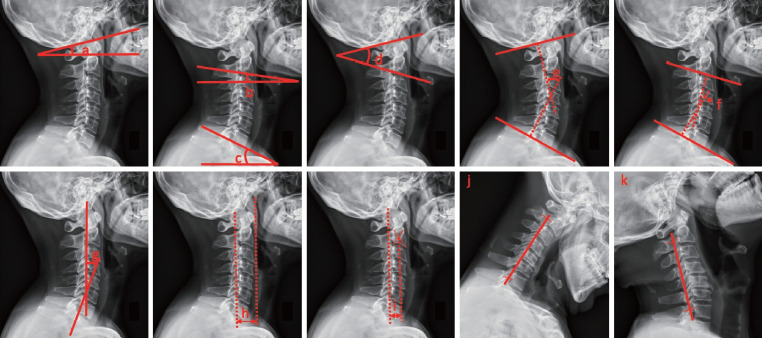

目的:应用纵向数据k均值(K-means for longitudinal, KML)分析退行性颈椎病(DCM)椎板成形术后颈部疼痛和颈椎功能的预测因素。方法:在这项前瞻性队列研究中,我们收集了行颈椎椎板成形术的DCM患者的临床和影像学资料。根据日本骨科协会颈椎病评估问卷,提出了一种新的手术结果指标“颈部功能”,包括颈部疼痛和颈椎功能。我们将手术结果视为纵向而非横断面数据,并使用KML进行分析。根据颈部疼痛和颈椎功能的KML图,将患者分为预后好或预后差。结果:2016 - 2020年,104例患者行椎板成形术治疗DCM;然而,35例患者因随访缺失或数据不完整而被排除。作者发现,中央管狭窄(优势比[OR], 17.93;95%置信区间[CI], 1.26-254.73;p=0.03)和术前颈部疼痛(OR每增加1点=1.49;95% ci, 1.12-1.99;p=0.006)为2个阴性预测因素,屈曲时k线阳性为阳性预测因素(OR, 0.11;95% ci, 0.01-0.87;P =0.036)对椎板成形术后颈部功能的影响。结论:椎管中央管狭窄、术前颈部疼痛和屈曲时的k线可预测椎板成形术后颈部疼痛和颈椎功能。为了获得更好的颈部功能手术结果,作者建议利用这些决定因素作为DCM手术入路选择的指导框架。

Results: From 2016 to 2020, 104 patients underwent laminoplasty for DCM; however, 35 patients were excluded because of loss to follow-up or incomplete data. The authors found that central canal stenosis (odds ratio [OR], 17.93; 95% confidence interval [CI], 1.26-254.73; p=0.03) and preoperative neck pain (OR per 1 point increase=1.49; 95% CI, 1.12-1.99; p=0.006) were 2 negative predictive factors and that a positive K-line during flexion was a positive predictive factor (OR, 0.11; 95% CI, 0.01-0.87; p=0.036) for neck function after laminoplasty.

Conclusion: Central canal stenosis, preoperative neck pain and a K-line during flexion were found to be predictive of postoperative neck pain and cervical spine function after laminoplasty. To achieve better surgical outcomes for neck function, the authors suggest the utilization of these determinants as a guiding framework for the selection of surgical approaches for DCM.